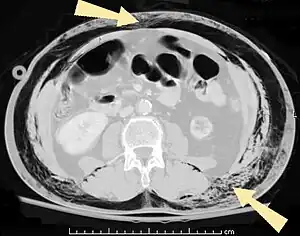

Significant cases of subcutaneous emphysema are easy to diagnose because of the characteristic signs of the condition.[1] In some cases, the signs are subtle, making diagnosis more difficult.[13] Medical imaging is used to diagnose the condition or confirm a diagnosis made using clinical signs. On a chest radiograph, subcutaneous emphysema may be seen as radiolucent striations in the pattern expected from the pectoralis major muscle group. Air in the subcutaneous tissues may interfere with radiography of the chest, potentially obscuring serious conditions such as pneumothorax.[18] It can also reduce the effectiveness of chest ultrasound.[27] On the other hand, since subcutaneous emphysema may become apparent in chest X-rays before a pneumothorax does, its presence may be used to infer that of the latter injury.[13] Subcutaneous emphysema can also be seen in CT scans, with the air pockets appearing as dark areas. CT scanning is so sensitive that it commonly makes it possible to find the exact spot from which air is entering the soft tissues.[13] In 1944, M.T. Macklin and C.C. Macklin published further insights into the pathophysiology of spontaneous Macklin's Syndrome occurring as a result of a severe asthmatic attack.